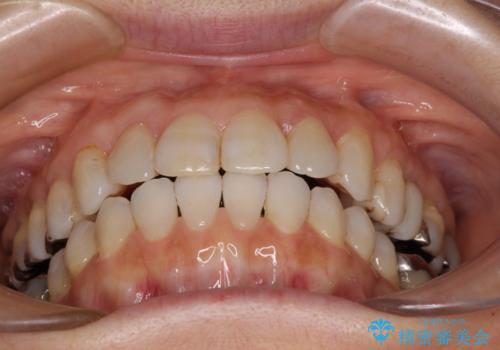

前歯の突出感と上下の隙間 インビザラインによる矯正治療

- 前歯の上下スペースと前歯の隙間を気にして来院された患者様です。

インビザラインにより上下の前歯の隙間を閉じながら、IPRを用いて口元の突出感を合わせて改善していくこととしました。

上下の隙間に舌が入り込むことが、すきっ歯やオープンバイトの原因であったため、舌の筋肉のトレーニングも並行して行い、後戻りの抑制を図りました。